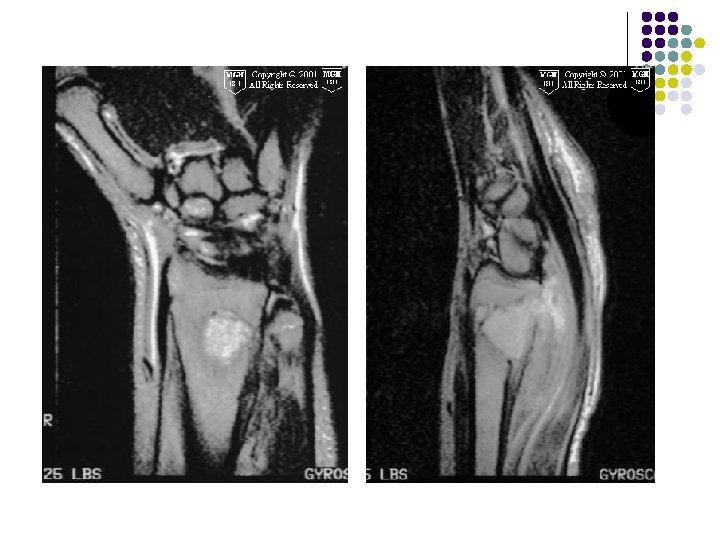

Radiographic Findings: Wrist Films: l Lobulated lytic lesion of the distal radius abutting the articular surface and extending from the epiphysis into the proximal metaphysis. l matrix calcification are seen. MR: l The lesion demonstrates low signal on T 1 weighted images and high signal on T 2 weighted images with rings and arcs compatible with chondroid matrix. l No extra-osseousoft tissue mass is seen.

T 2 -weighted coronal MRIs of the wrist show a giant cell tumor located in a subarticular position in the distal radius. The lesion is heterogeneous and hyperintense.